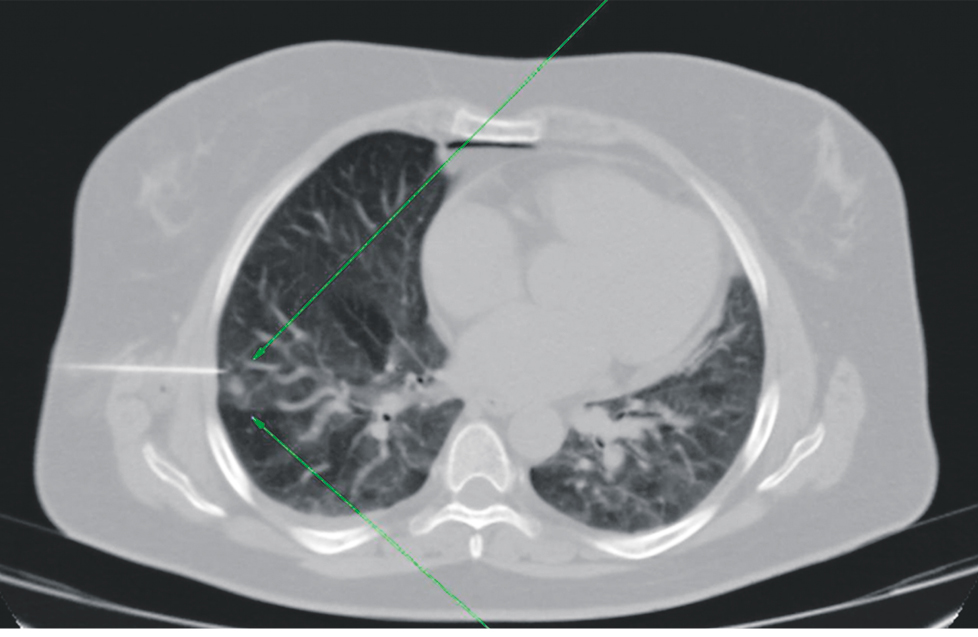

Методика маркировки периферических новообразований легких посредством предоперационной установки системы «якорной метки»1. Непосредственно перед оперативным вмешательством пациентам выполнялась визуализация патологического участка легкого по описанной выше методике (рис. 3) с последующей трансторакальной установкой системы «якорной метки» под местной анестезией 20 мл 0,5 % раствора лидокаина (рис. 4, 5).

Рис. 3. Компьютерная томограмма груди в аксиальном срезе, пациент И., 44 года. Периферическое новообразование S4 правого легкого по типу «матового стекла» (зеленые стрелки)

Fig. 3. Axial computed tomography scan of the chest, Patient I, 44 years old. Peripheral neoplasm S4 of the right lung with ground-glass opacity (green arrows)